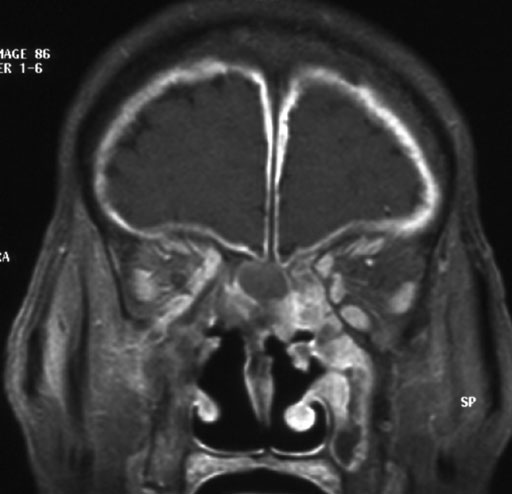

画像所見としては鼻副鼻腔にびまん性軟部濃度肥厚が見られ,一部多結節様を示す.両側篩骨洞領域では軟部濃度腫瘤様に認められる.内部濃度は比較的均一で明らかな石灰化は認められない.後上部において鼻中隔穿孔を認め,右眼窩内側壁,篩骨篩板,鷄冠基部,蝶形骨平面,前頭洞後壁の浸食性,破壊性変化を伴う.右眼窩壁の浸食性変化は眼窩尖部レベルに及び,眼窩内側から下壁に沿った眼窩内円錐外腔を中心とした眼窩内浸潤性軟部濃度病変を認める.ただし,眼窩尖部レベルでは視神経周囲の脂肪層の混濁,消失を来しており,右視力低下に関連すると思われる.同様にして下眼窩裂の脂肪層も消失している.鼻副鼻腔に比較的広範な浸潤性軟部濃度肥厚を認め,鼻中隔を含む多部位における骨浸食性変化,眼窩への浸潤性変化などからWegener's granulomatosisが考慮される.さらに,図4及び5において広範な髄膜肥厚が疑われる.頭痛を訴えていることよりWegener's granulomatosisの髄膜浸潤と考えられる.その後施行された造影後T1強調像(図)においても広範な髄膜の肥厚と増強効果が確認された.本例ではcANCA(circulating antineurtrophil cytoplasmic antibodies)の上昇,鼻内生検病理像などから診断が得られた.その後,ステロイド投与により症状の軽減が見られている.浸潤性真菌性副鼻腔炎は鑑別疾患となるが,本例はとくに免疫不全を示す状態ではなかった.また,鼻腔円蓋部を中心に腫瘤様所見を認め,篩骨篩板の破壊が見られることから嗅神経芽腫も鑑別疾患として含まれると思われ,年令にも著しい矛盾はないが,病変が広範かつ多中心性で,骨浸食性変化も腫瘤様軟部濃度病変に隣接しない部位を含めた多部位にわたることなどから考えがたい.

本例では鼻副鼻腔病変を認め,篩骨篩板や前頭洞後壁破壊を示し,直接浸潤(上記2型)が疑われるが,髄膜所見が広範かつびまん性であることから髄膜における肉芽形成(上記3型)も伴っていると思われる.画像上は造影後T1強調像において広範な髄膜肥厚と増強効果を示す.